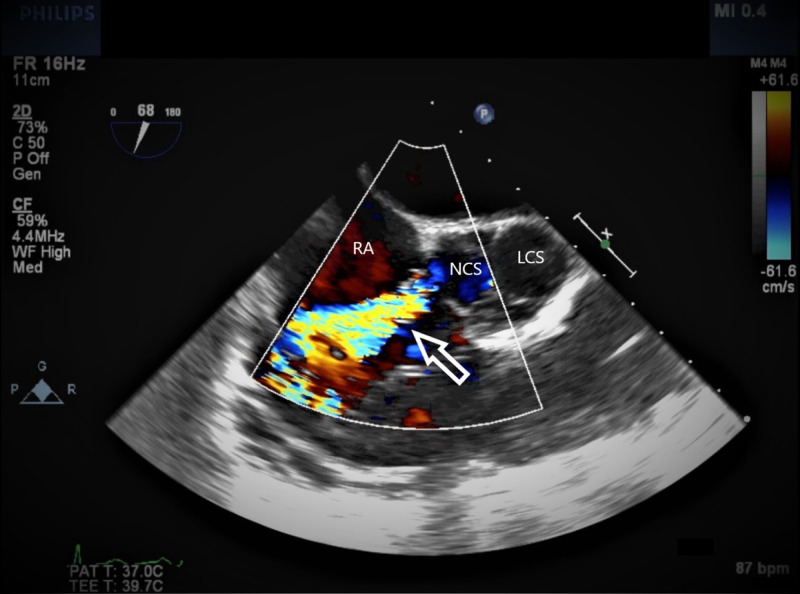

Figure 2. TEE with color Doppler.

The arrow indicating the high-velocity jet from the NCS into the RA through the ruptured SVA.

TEE, transesophageal echocardiogram; SVA, sinus of Valsalva aneurysm; RA, right atrium; NCS, noncoronary sinus; LCS, left coronary sinus.